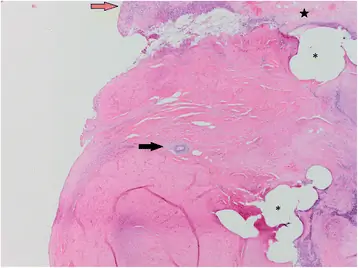

Животное 2 было помещено в закрытую больницу CNPRC с неспецифической травмой, связанной с укушенными ранами и рваными ранами правой ноги, левой щеки и шеи, через 1 день после возвращения в домашнюю клетку, то есть через 7 дней после размещения Васалгеля. При осмотре выявлено сильное опухание, ощутимое в левом месте операции, распространяющееся в мошонку. Невозможно определить, была ли опухоль связана с травмой в результате драки с другими мужчинами, гранулемы спермы или гидроцеле. Хотя во время физического осмотра не было обнаружено никаких внешних признаков травмы области половых органов, нельзя исключать возможную внутреннюю травму от агрессии между мужчинами. Была выбрана исследовательская операция, в результате которой была предпринята попытка выполнить традиционную вазэктомию, как описано выше (с использованием 4-0 проленов), из-за наличия гидроцеле. Предполагаемый семявыносящий проток был представлен для гистопатологии. Гистопатология показала, что в семенном канатике было несколько областей пиогранулематозного воспаления с примесью свободных сперматид, фибрина и кровоизлияний вдоль поверхности семенного канатика, что подтверждает наличие левой сперматозоидной гранулемы (рис. 1). Смежные с этими областями, но не связанные с каким-либо воспалением, были небольшими нерегулярными очагами от базофильного до амфофильного от зернистого до кристаллического материала, предположительно являющегося Васалгелем (рис. 2). Таким образом, оказалось, что воспаление было связано с наличием внепросветной спермы, а не с наличием Vasalgel. Изучив гистопатологическое и медицинское заключение, было установлено, что присутствие Васалгеля было случайным послеоперационным осложнением.

Животное 2: Обильная коллагеновая строма, окруженная пиогранулематозным воспалением (оранжевая стрелка) и фибрин (черная звезда). Свободные места представляют области, которые содержали швы (звездочка). В центре изображения находится небольшая глобула от базофильного до амфофильного материала (черная стрелка, предположительно Vasalgel). H & E, 40x

Изображение в полном размере